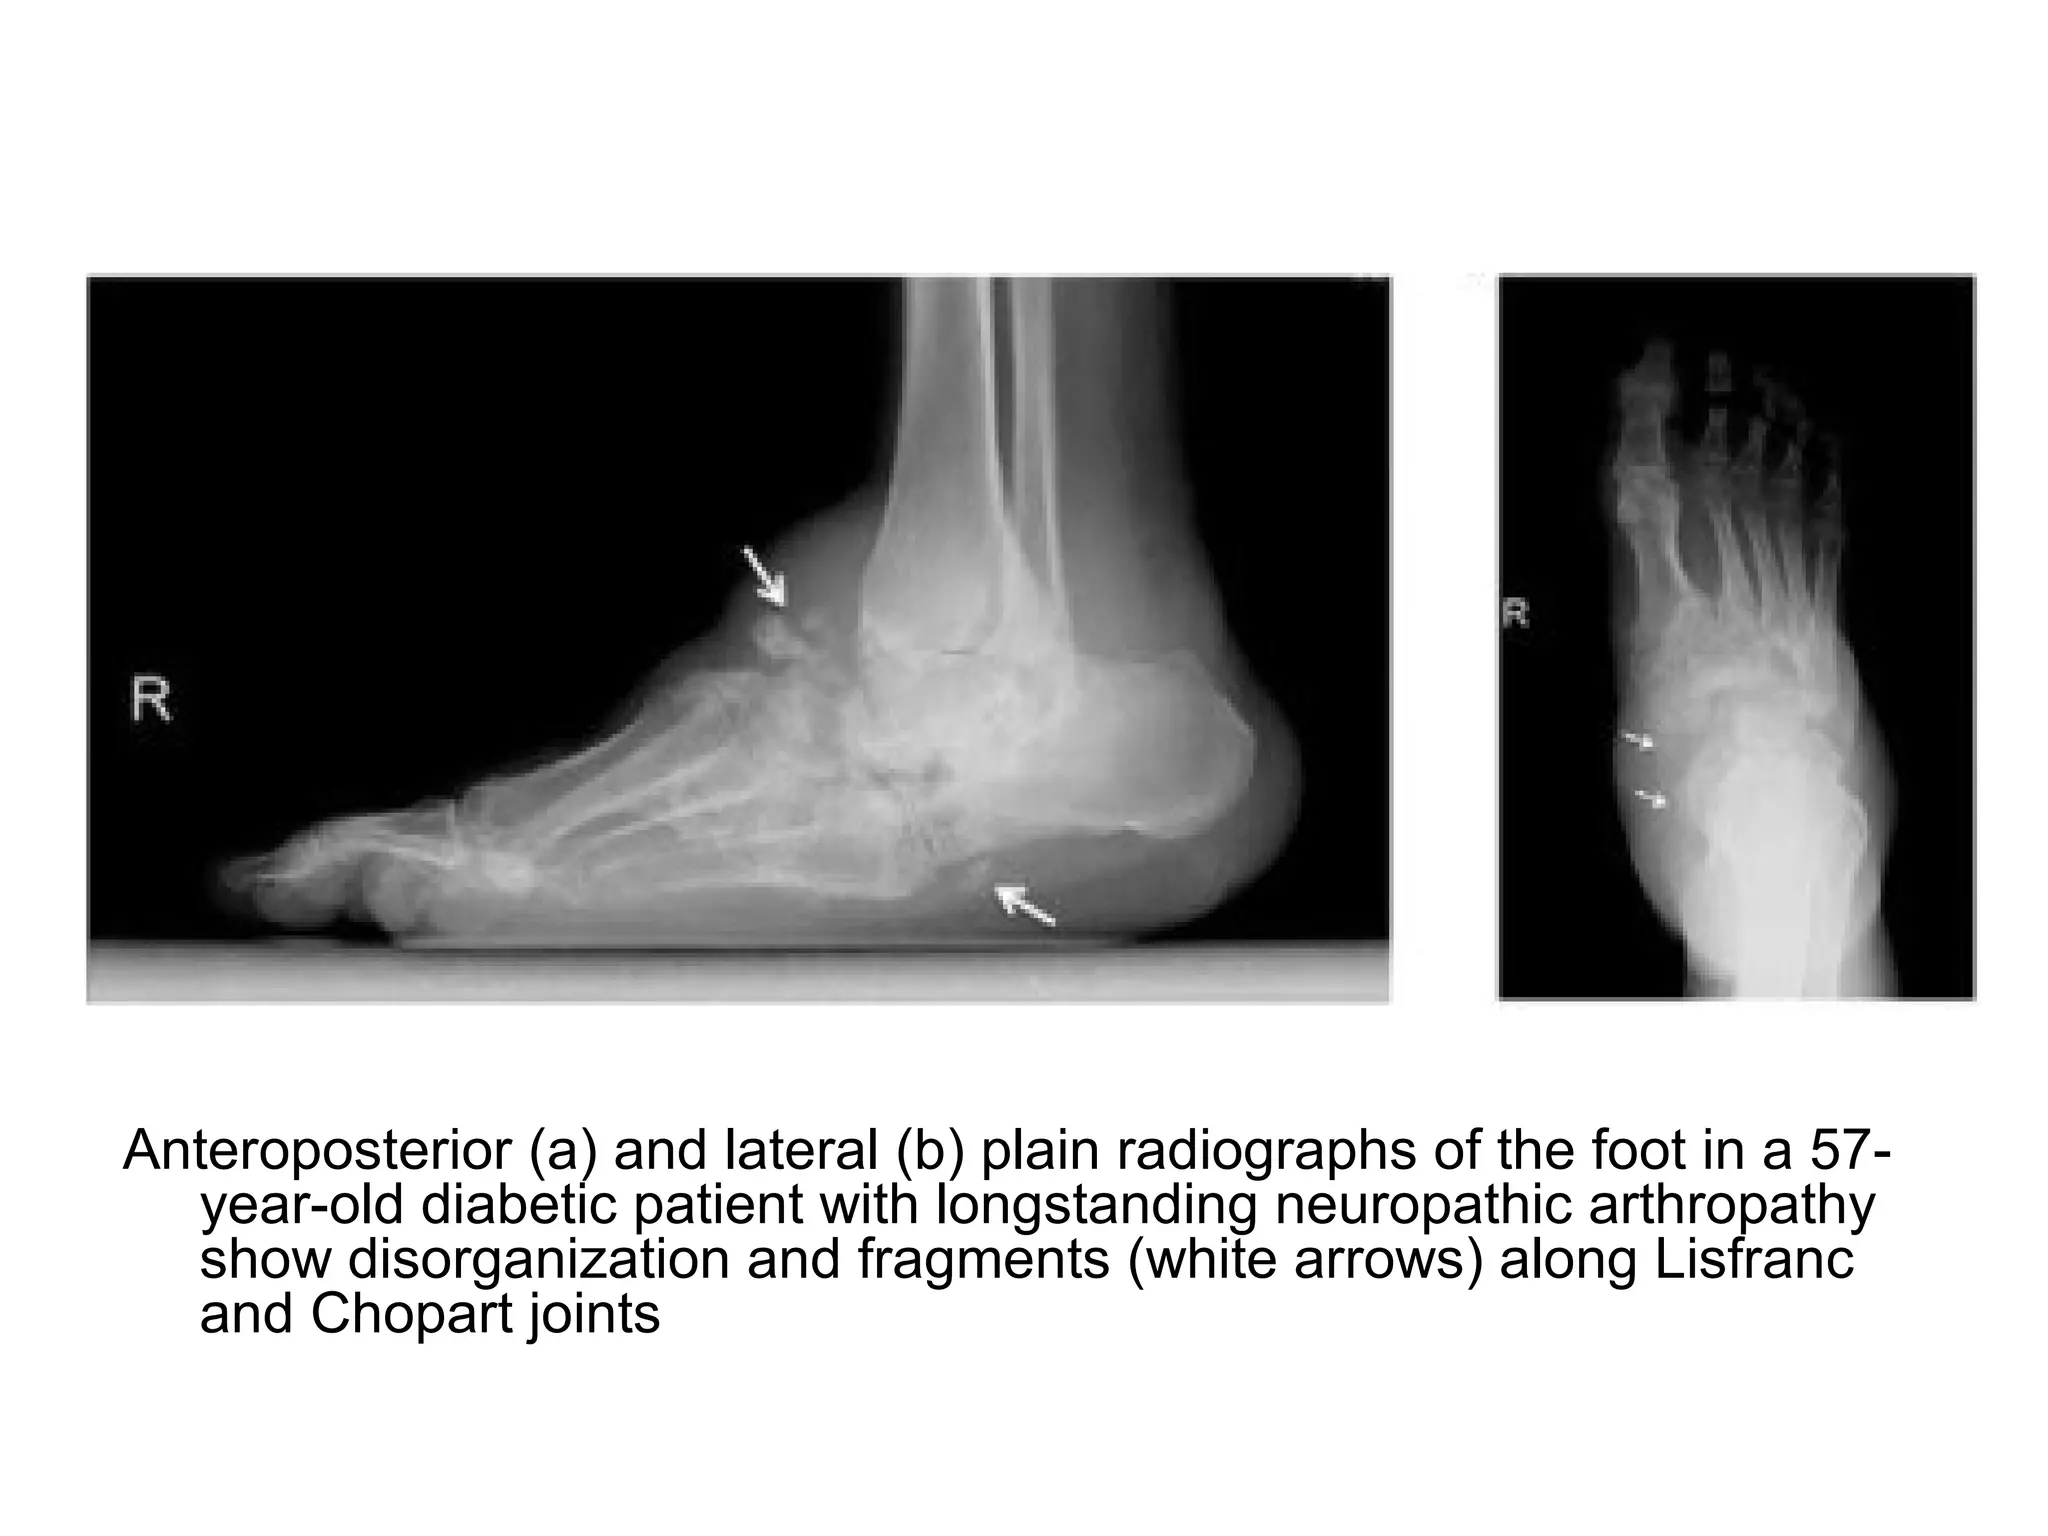

Anteroposterior (a) and lateral (b) plain radiographs of the foot in a 57-

year-old diabetic patient with longstanding neuropathic arthropathy

show disorganization and fragments (white arrows) along Lisfranc

and Chopart joints

4-Radiographic Features : 6D

1-Dense bones (subchondral sclerosis)

2-Degeneration

3-Destruction of articular cartilage

4-Deformity (pencil-point deformity of metatarsal

heads)

5-Debris (loose bodies)

6-Dislocation (Lisfranc Fracture / Dislocation)

a) Diabetes neuropathy : usually foot

b) Tertiary syphilis (tabes dorsalis) : usually knee

and spine